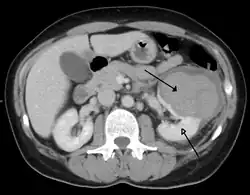

| Trauma abdominal resultando em uma contusão no rim direito (seta aberta) e sangue ao redor do rim (seta fechada), conforme visto em tomografia computadorizada. | |

Os rins também podem ser lesionados; eles são parcialmente, mas não completamente, protegidos pelas costelas.[6] Lacerações e contusões renais também podem ocorrer.[11] Lesões renais, um achado comum em crianças com trauma abdominal contuso, podem estar associadas a sangue na urina.[10] Lacerações renais podem estar associadas a urinoma ou vazamento de urina para o abdômen.[4] Um rim fragmentado é aquele com múltiplas lacerações e uma fragmentação associada do tecido renal.[4]